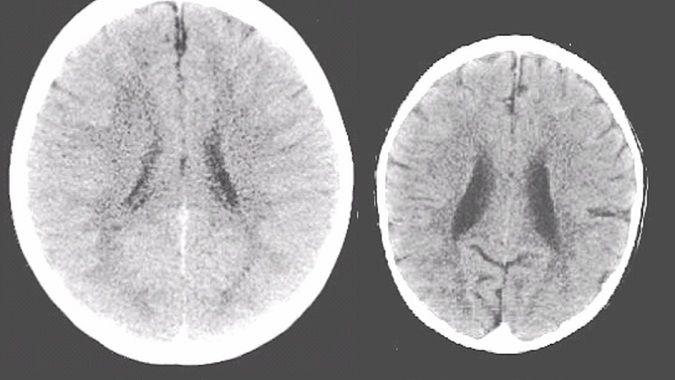

Przytulanie i bliski kontakt z maluchem mają kluczowe znaczenie dla jego prawidłowego rozwoju. Psychologowie dziecięcy są przekonani, że pierwsze trzy lata życia są okresem, kiedy bliski kontakt z co najmniej jednym z rodziców odgrywa dla dziecka bardzo ważną rolę, rzutując na dalszy rozwój emocjonalny i intelektualny malucha. Za przykład może posłużyć zestawienie zdjęć mózgu dwójki dzieci: jedno z nich wychowywało się w pełnej rodzinie, drugie w sierocińcu.

Różnice widać gołym okiem. Oba zdjęcia prezentują mózgi 3-letnich dzieci. Zdjęcie po lewej stronie pokazuje, w jaki sposób rozwija się maluch, który ma stały kontakt z bliskimi, jest przez nich przytulany i noszony na rękach.

Po lewej - mózg dziecka z pełnej rodziny, po prawej mózg 3-latka wychowywanego w domu dziecka.

Po lewej - mózg dziecka z pełnej rodziny, po prawej mózg 3-latka wychowywanego w domu dziecka. © FB